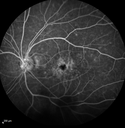

68 year old man with decreased vision for 2 months. Cataract surgery was 4 months ago. He is also diabetic. Vision is 20/32 OD 20/100 OS. The left eye has a serous retinal detachement and CME. The right eye shows signs of uveitis on FA with patchy leakage and staining of the nerve.

Pseudophakic CME with serous retinal detachment - FA shows leakage in both eyes421 views68 year old man with 2 months of vision loss. FA shows CME, notice that the nerve also leaks. This is typical for pseudophakic inflammatory cystoid macular edema00000

Pseudophakic CME with serous retinal detachment - FA shows leakage in both eyes441 views68 year old man with 2 months of vision loss. FA shows CME, notice that the nerve also leaks. This is typical for pseudophakic inflammatory cystoid macular edema00000